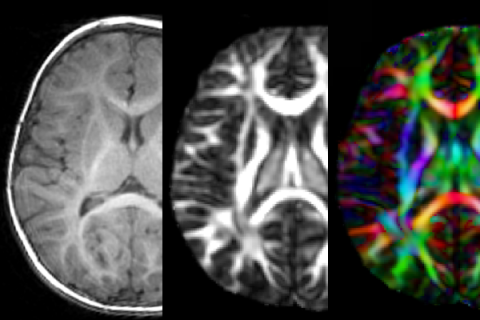

Diffusion

- ADC mapping

- Diffusion tensor imaging (DTI)

- High-angular resolution diffusion imaging (HARDI)

- Diffusion kurtosis imaging (DKI)

- Neurite orientation dispersion and density imaging (NODDI)

- Intravoxel incoherent motion (IVIM)

- Segmented diffusion-weighted imaging (RESOLVE)